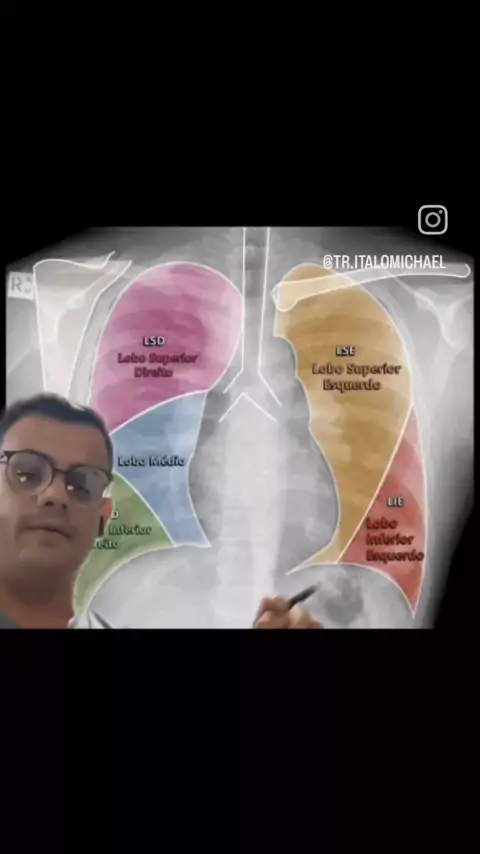

tudo bem? Eu me chamo Ítalo Michael sou técnico em radiologia,E hoje vamos falar um pouquinho sobre raio-x do tórax e também falar sobre anatomia radiológica e patologia apresentada na imagem,mas Lembrando que quem fecha o diagnóstico são os médicos não sou eu técnico e nem os tecnólogos em radiologia o meu intuito é te ensinar a interpretar este tipo de imagem em radiologia. TR° Ítalo Michael CRTR -07244t #raiox #anatomia #radiologia #medicinaporamor #viral